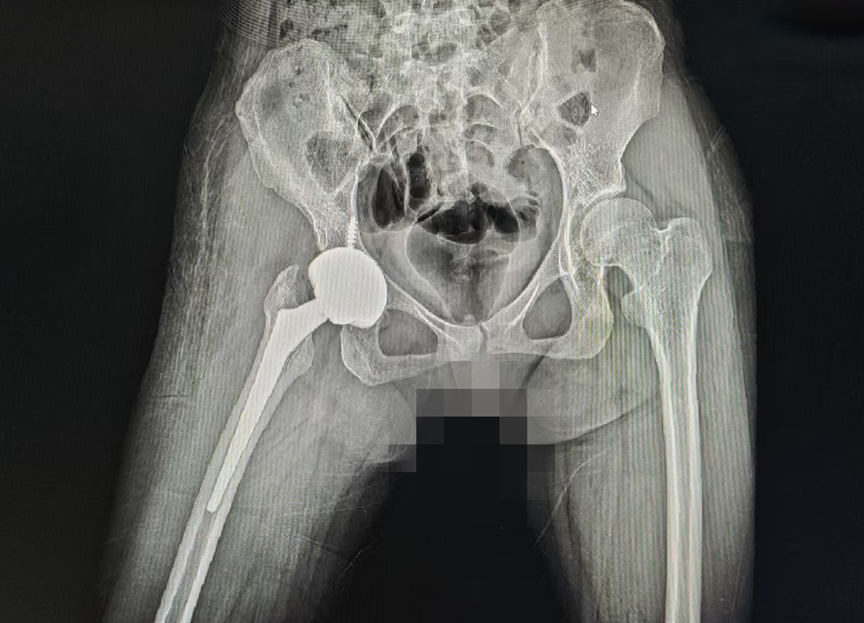

术后

入院后,医院手术团队第一时间为小舒进行了全面、细致的检查,结合她的病情、身体状况及康复需求,量身制定了机器人辅助髋关节置换治疗方案。与传统手术不同,手术机器人可提前进行精准的术前规划,精准测算假体的大小、安装位置,避免了人工操作的误差;术中,机器人实时监测手术操作,全程辅助医生完成假体植入等关键步骤,既保证了手术的精准度,又最大程度减少了对周围组织的损伤,真正实现了精准、微创、不截骨。

术后,医院依托快速康复理念和责任制整体护理模式,为小舒制定了个性化康复计划,医护人员每天定时查房、指导康复训练,耐心讲解术后注意事项,细致呵护她的恢复过程。惊喜的是,术后不久,小舒就能顺利下地行走,康复进度远超同类先髋高脱患者。“比我想象中好太多了,手术一点都不疼,恢复得也特别快。”小舒脸上洋溢着久违的笑容。